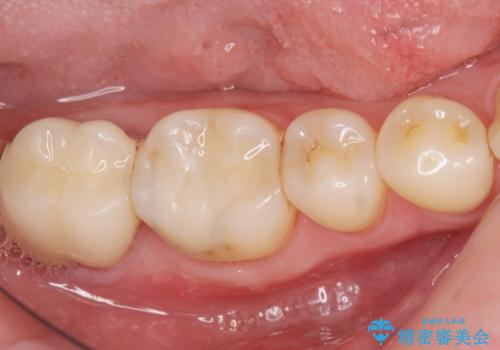

歯ぐきの深い位置まで虫歯が 歯周外科→被せもの による奥歯の治療

多発した縁下カリエス 歯周外科を併用する虫歯治療